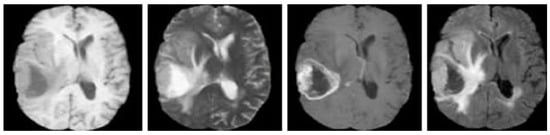

Modalities of the BraTS 2020 database are equipped with manual segmentation of lesions and consist of 125 subject data without the manual ground truth which can be used for comparison. Example MRI scans of the BraTS 2020 database are included in Figure 3.

Figure 3.

Example MRI brain scans of BraTS 2020 database [35].